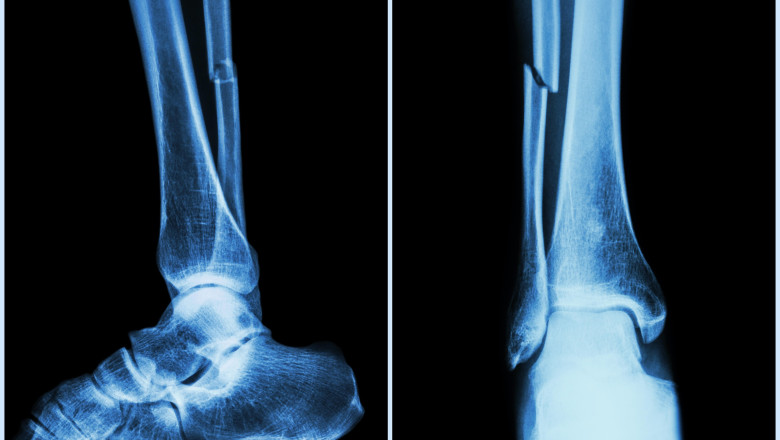

Cercetătorii chinezi susţin că au dezvoltat un adeziv osos care poate fi folosit pentru a trata fracturile şi fragmentele osoase zdrobite, printr-o procedură care durează doar trei minute. Echipa de cercetare din provincia Zhejiang, sub conducerea medicului ortoped dr. Lin Xianfeng, de la spitalul Sir Run Run Shaw, din China, a anunţat că a dezvoltat un adeziv medical inovator care ar putea schimba radical modul în care sunt tratate fracturile, potrivit News.ro.

Substanţa, denumită „Bone-02”, promite să repare fragmentele de os în doar câteva minute, reducând necesitatea intervenţiilor chirurgicale invazive şi a implanturilor metalice.

În testele de laborator şi în primele încercări clinice, substanţa a demonstrat atât siguranţă, cât şi eficacitate, potrivit echipei. Într-un studiu, procedura a fost finalizată în mai puţin de trei minute, comparativ cu tratamentele convenţionale care implică incizii mari şi fixare cu plăci şi şuruburi metalice.